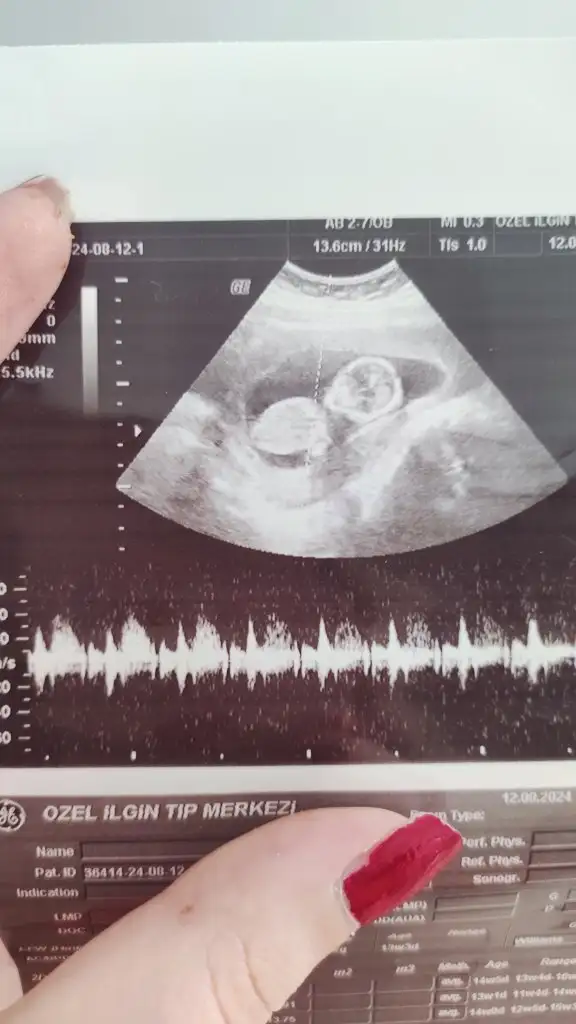

5 ve 14. haftaya kadar olan ultrason fotolarınızı paylaşın. Vajinadan mı yoksa karından mı çekildiğini ve kaç haftalık olduğunu da mutlaka belirtin.